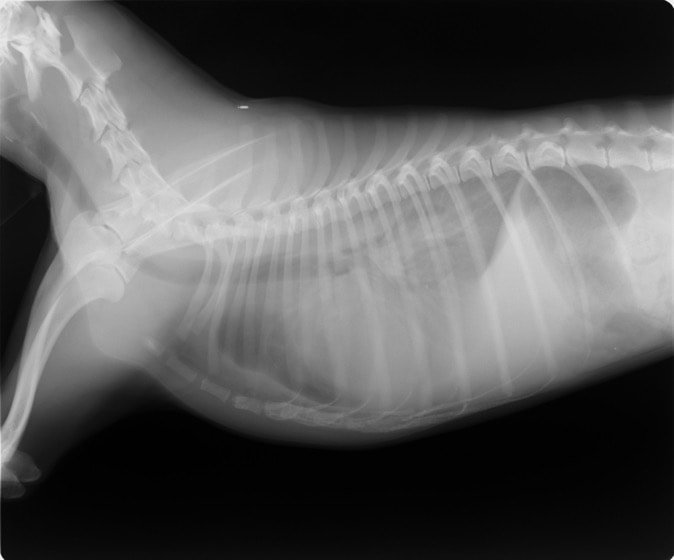

腹部と胸部を隔てている横隔膜が何らかの原因で裂け、腹部臓器(肝臓、小腸、胃など)が胸腔内に脱出してしまう病気です。脱出した臓器による肺・心臓の圧迫や、臓器の機能障害により、様々な呼吸器症状や消化器症状を示します。原因には外傷性と先天性の2つがあり、犬・猫で最も多いのは交通事故による外傷性横隔膜ヘルニアです。犬・猫の室内飼育が一般的になったことで交通事故が減り、それに伴い本疾患に遭遇することも減りましたが、屋外を自由に出入りしている猫では注意が必要です。屋外から帰った猫がお腹で呼吸をしている、苦しそうにしているなど、少しでも症状がある場合には早めに動物病院を受診し、レントゲン検査を受けられることをお勧めいたします。以下に交通事故が原因 と考えられる外傷性横隔膜ヘルニアの猫の症例をご紹介致します。

術前レントゲン

腹部臓器が胸腔内に脱出し、腹部と胸部の境界および心臓や肺の陰影が不明瞭になっています。また、胸腔内に消化管のガス陰影が認められます。